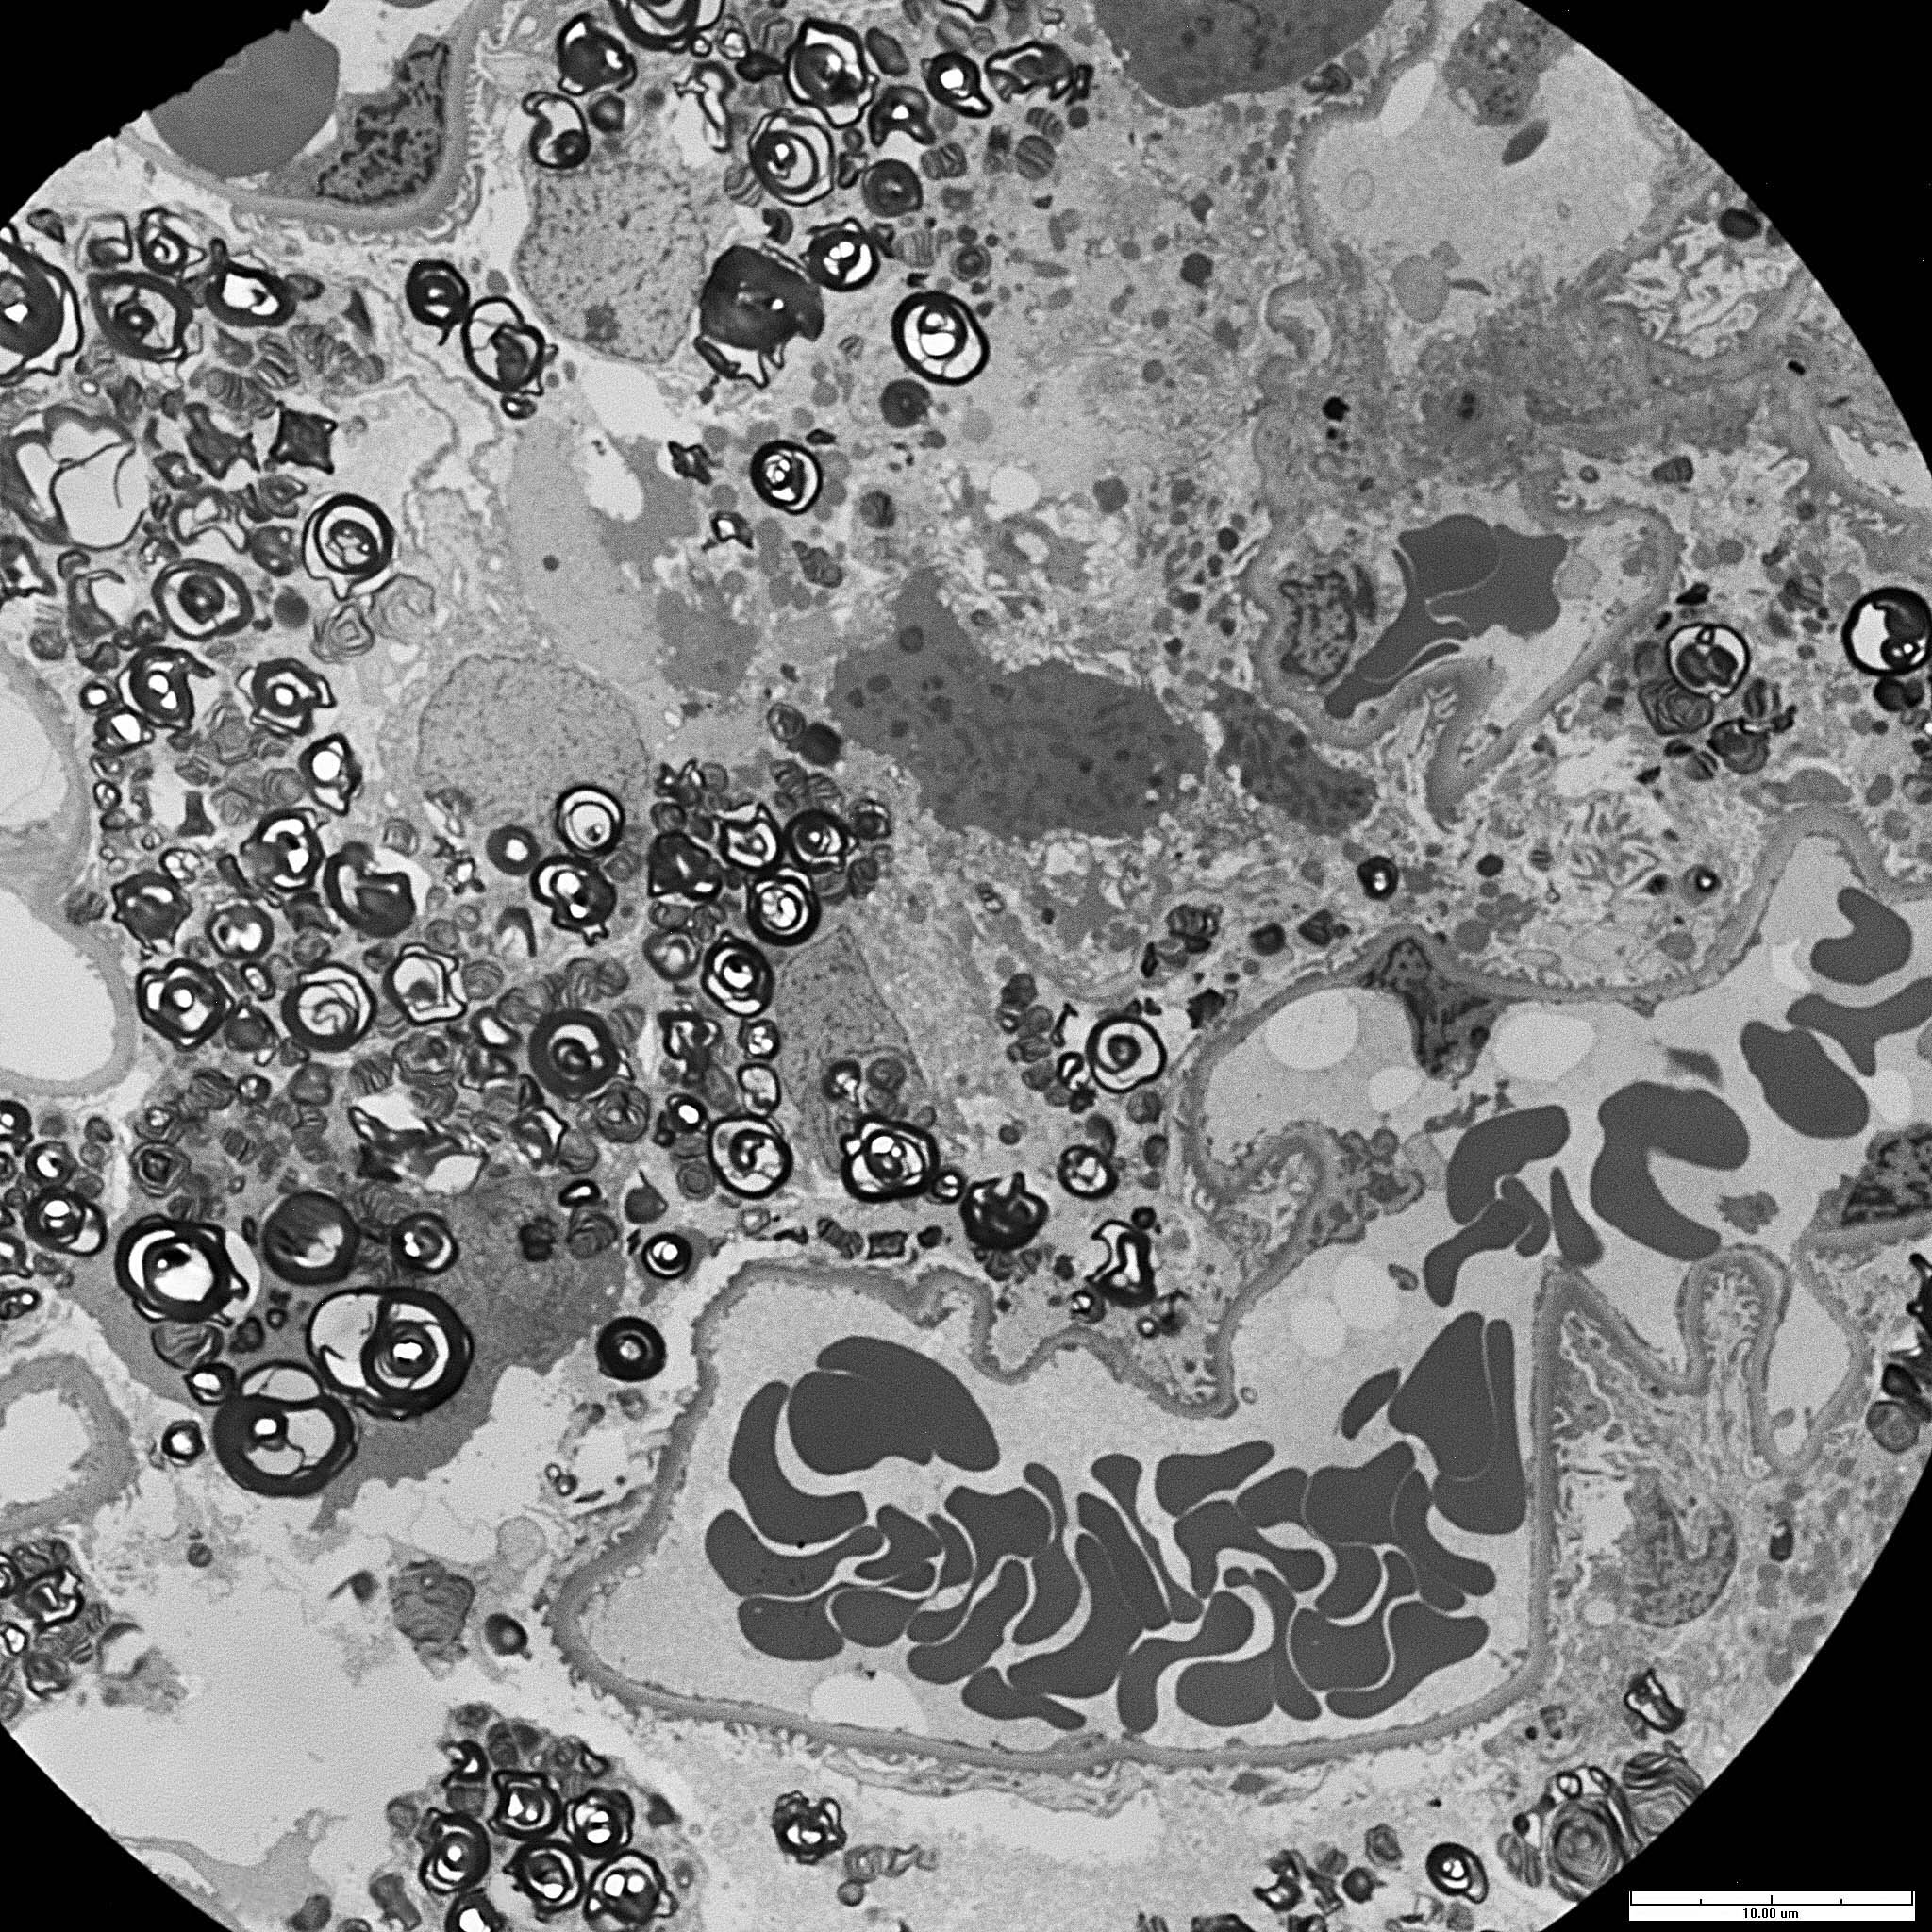

Fabry disease is an X-linked deficiency of alpha-galactosidase A leading to intracellular accumulation of glycosphingolipids. Clinical manifestations are systemic because this enzyme is present in lysosomes throughout the body; they include painful neuropathies, skin lesions (classically angiokeratomas), cardiovascular and renal disease (commonly proteinuria). By light microscopy, the accumulated galactosyl ceramide appears as vacuolization of podocytes and tubular cells because it is extracted by the xylene used in processing. By electron microscopy, lamellated inclusions called myelin or zebra bodies are most prominently present in podocytes, but are also variably present in endothelium, tubules and interstitial cells. Genetically engineered alpha-galactosidase A can now be used to treat patients, resulting in decreased disease manifestation.